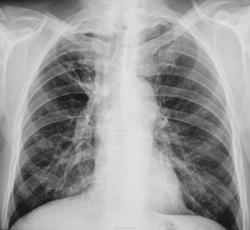

Пол пациента: Мужской пол Тип патологии: Другое Область исследования: Грудная клетка и верхние дыхательные пути Методы исследования: Rg Ранее болел туберкулёзом. Сегодня был направлен терапевтом с диагнозом пневмонии https://radiomed.ru/sites/default/files/styles/case_slider_image/public/user/12/2.dscn1413.jpg?itok=ddIwdutI https://radiomed.ru/sites/default/files/styles/case_slider_image/public/user/12/3.dscn1414.jpg?itok=BaDHOskS https://radiomed.ru/sites/default/files/styles/case_slider_image/public/user/12/4.dscn1415.jpg?itok=72LWEAHd ID:27835 Чт, 11/04/2013 - 09:53 #1 НБ Не на сайте Был на сайте: 11 лет 5 месяцев назад Зарегистрирован: 07.11.2012 - 19:55 Публикации: 84 утолщена апикальная плевра. Справа в верхней доле фиброз?. Но на ТГ не виден ВДБ, нет ли ателектаза в/доли. Н.Б. Чт, 11/04/2013 - 16:16 #2 brainmodel Не на сайте Был на сайте: 2 месяцев 2 недели назад Зарегистрирован: 18.03.2010 - 22:04 Публикации: 2881 Архив. Затем все разговоры. Verum plus uno esse non potest. Чт, 11/04/2013 - 19:26 #3 maker4ik Не на сайте Был на сайте: 8 лет 7 месяцев назад Зарегистрирован: 19.10.2011 - 17:49 Публикации: 2682 Не увидела пневмонию. И свежих очагов тоже. Чт, 11/04/2013 - 19:55 #4 Сергей Кузьминов Не на сайте Был на сайте: 1 год 2 недели назад Зарегистрирован: 06.10.2012 - 15:51 Публикации: 11813 Активного лёгочного процесса нет.Посттуберкулёзные изменения есть.

утолщена апикальная плевра. Справа в верхней доле фиброз?. Но на ТГ не виден ВДБ, нет ли ателектаза в/доли.

Не увидела пневмонию. И свежих очагов тоже.

Активного лёгочного процесса нет.Посттуберкулёзные изменения есть.